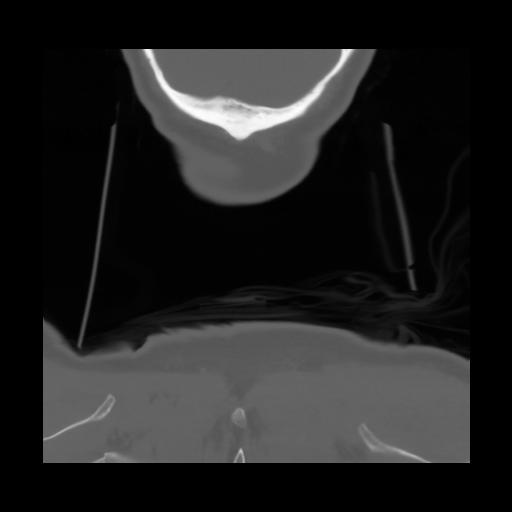

13 P.BLANDAS,,Coronal,2.000,P.BLANDAS,Coronal,